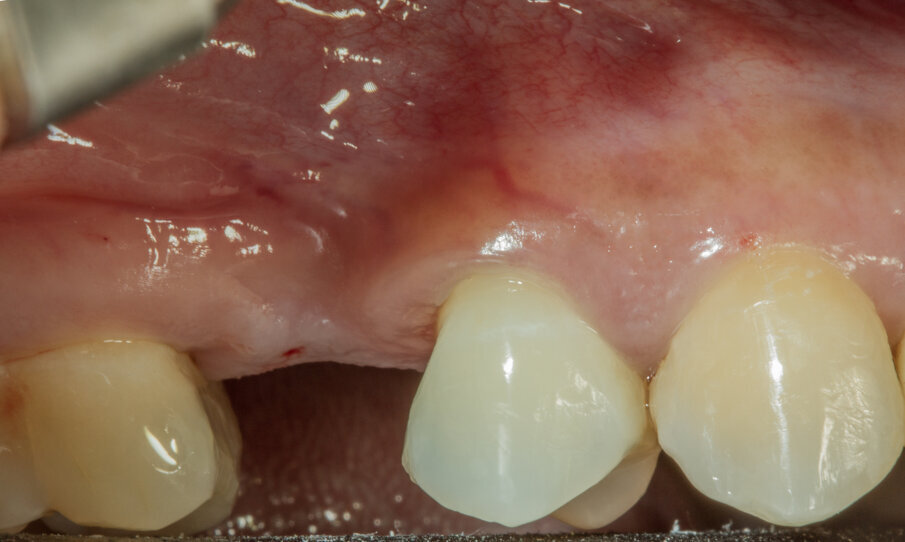

Caso clinico Viene presentato un caso clinico di GBR per la ricostruzione volumetrica di una cresta ossea atrofica mascellare con inserimento di biomateriale osseo di natura eterologa (OsteoBiol Gen-Os) e di una lamina corticale soft collagenata (OsteoBiol Lamina Soft) stabilizzata sulla sede del difetto osseo con utilizzo di colla di fibrina (Tisseel, Baxter) e con 2 chiodini di fissazione crestali. La paziente N.H. di anni 42, sesso femminile, non fumatrice, ASA 1, si presentò alla mia osservazione per la sostituzione di un elemento dentale, 2° premolare superiore destro, estratto più di 15 anni prima (Figg. 2, 3). Dall’esame clinico si osserva un marcato riassorbimento in senso orizzontale del sito edentulo, lo stato dei tessuti gengivali è di salute, non vi sono lesioni parodontali sui denti contigui. L’esame CBCT conferma la perdita di oltre il 50% del tessuto osseo vestibolare pur rimanendo conservata l’altezza verticale della cresta (Fig. 4).

Fig. 2 - Situazione iniziale.

Fig. 3 - Situazione iniziale. Vista occlusale.